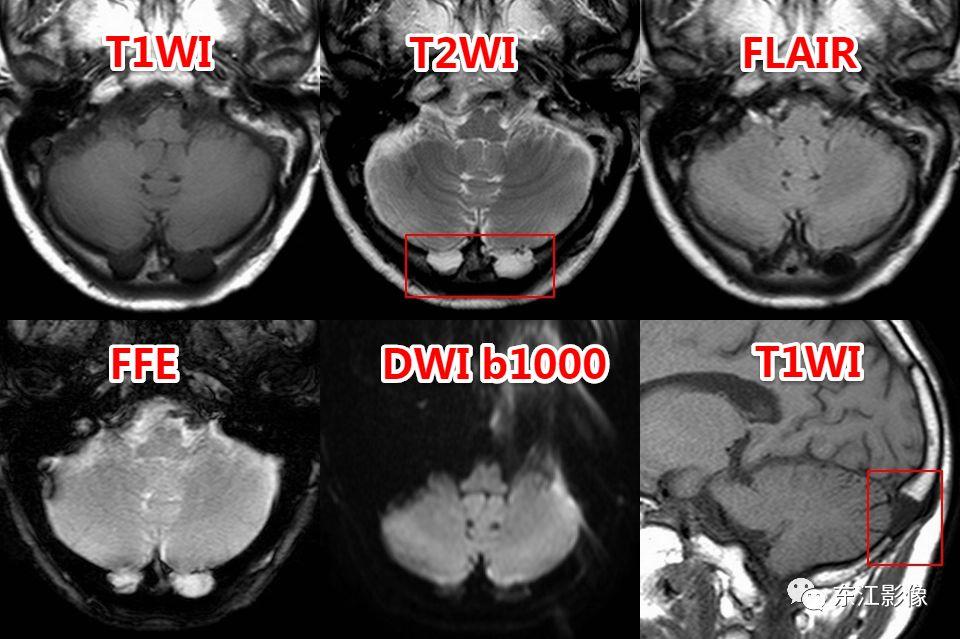

5. 脑脊液流动伪影

- 脑脊液流动伪影主要见于T2WI、FLAIR,主要是长TE序列容易出现流空效应的缘故。

- 但由于脑脊液流动方向、速率不一等因素的影响,呈现为非脑脊液信号影像,部分呈囊样。

- 常见于第三脑室、侧脑室室间孔旁区、脑干周围脑池(这些区域结构复杂)。

- 鉴别要点,T1WI、增强未能辨认;DWI与邻近一致的无信号;无占位效应。

桥前池脑脊液流动伪影。